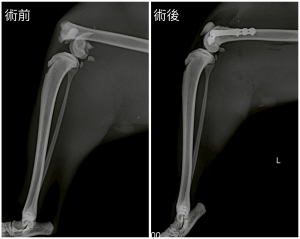

X光檢查顯示是股骨遠端生長板骨折,屬於Salter-Harris 第二型生長板骨折

米魯接受了骨板固定手術,骨折對位固定之後,貓貓很快就可以恢復行走功能,一個半月後再次拍攝 X 光就可以看到骨折處已經完全癒合啦